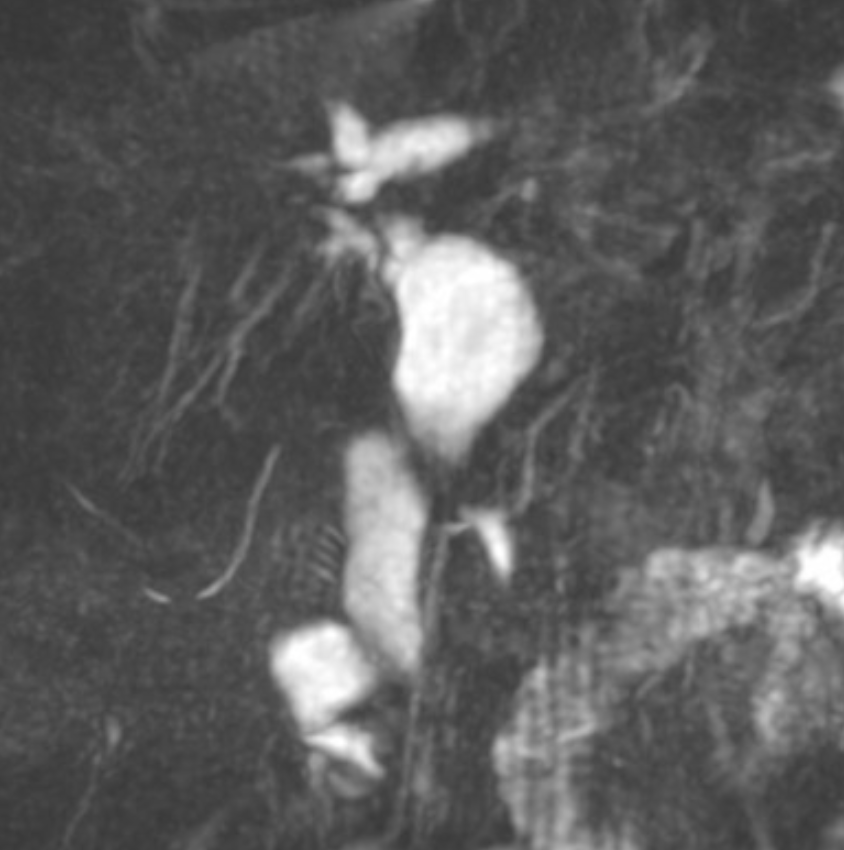

Biliary MR

Dx: type 4A choledochal cyst.